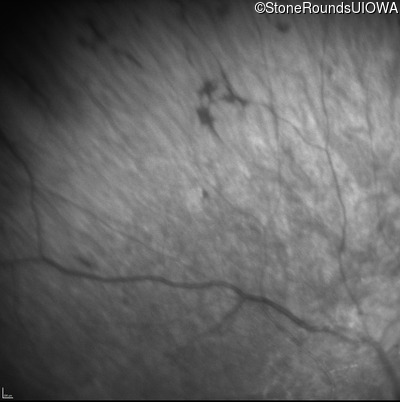

Infrared Fundus Photograph - Left - No Light Perception

Exemplar